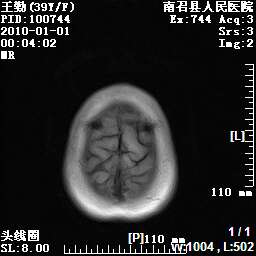

以下是引用随光逐影在2010-1-22 9:03:00的发言:[br]考虑左侧中颅窝(蝶骨翼区)脑膜瘤侵犯蝶骨翼并突入左侧眼眶。

以下是引用水过无痕在2010-1-22 14:55:00的发言:[br]一、定位:颅外占位;二、定性:恶性可能性大;三、组织来源:来源于左侧眼外直肌或其他部位;考虑为:横纹肌肉瘤>转移瘤>脑膜瘤.